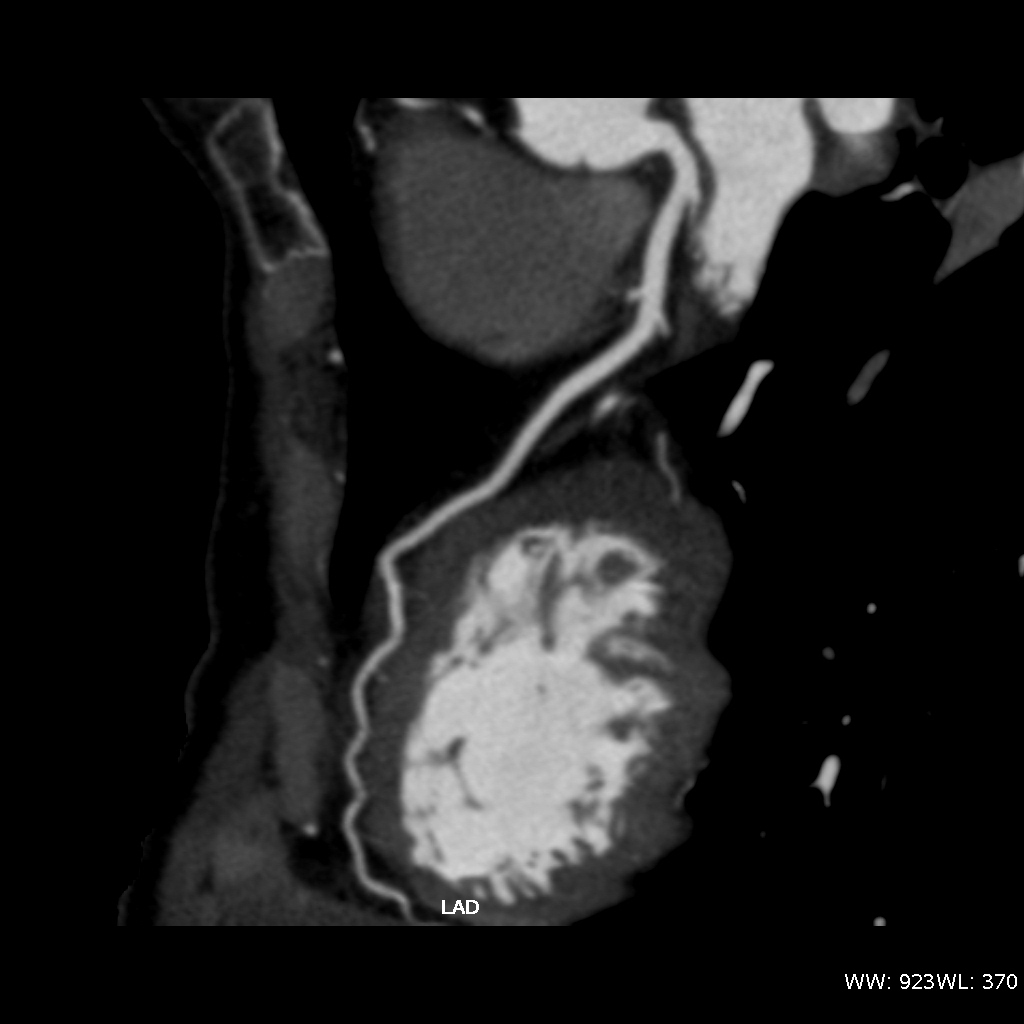

Fig. 3., 4., 5.: CT coronarography: Normal anatomy, volume rendered image and curved reformatted image Plaque causing stenosis on LAD coronary artery

The conventional imaging modality of the coronary vessels is cardiac catheterization (coronarography) which is still an absolute indication in acute coronary syndrome. During the examination besides identification of the symptom causing stenosis or occlusion (culprit lesion), it is also possible to perform dilatation with a balloon catheter or stent implantation to restore flow. If either of these procedures is carried out within 6 hours of symptom onset, myocardial tissue dearth can be prevented or minimalized. Coronarography of patients with stable angina is only recommended if a high risk of coronary disease persists clinically. CT coronarography can replace cardiac catheterization in low and medium risk patient groups who present with angina-like chest pain. The examination has a very high sensitivity and negative predictive value for coronary disease; therefore, it is a sensitive screening tool for patients who present with chest pain as a symptom of coronary stenosis. It can also uncover alternative diagnoses for chest pain syndromes. CT examination is not only good in representing the vascular lumen, but it can also detect non-stenosing but vulnerable (lipid rich) plaques by showing a special morphologic appearance. These lesions might remain hidden during coronarography, producing false negative results with regard to an existing significant atherosclerotic involvement.